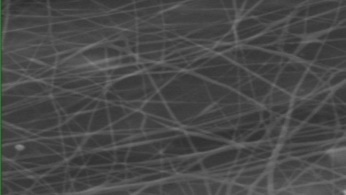

Morphology analysis was adapted from Aytac et al. (2019) [38]. The SEM analysis was conducted to detect electrospun nanofibers' fibre shape and diameter. The electrospun nanofibres from 18 runs were investigated individually by SEM (FEI, quanta 450, Czech). Images revealed the morphology of resultant nanofibers and measured their diameters in nanometres. The average number of records was calculated using a standard deviation estimation. The setting of the SEM machine was conducted on voltage 25.00 kv, magnification 23624 and width (8.3-9.3 mm).

Results of the SEM analysis are listed in table 2, with a wide range of fibre diameters starting from 87.2 nm (run 13) to 2500 nm (run 18). Run 18 did not produce true nanofibers due to the deficient concentration of PVA. The statistical analysis revealed that the effect of each polymer (factor) on the diameter size of the electrospun nanofiber was vast. Therefore, there is a correlation between factors A, B and C and fibre diameter as expressed in equation 5.

Fig. 3: Nanofibres SEM images with nanofiber diameter frequencies. The PVA, PEO and HPMC were symbolised as V, E and P. Data are given in mean±SD, n=3

The morphology of nanofibers would be affected by device parameters such as flow rate, voltage and distance from the collector. Also, nanofibres' properties could be changed due to temperature and humidity. The bead formation appears with a low concentration of PVA (run 2) or a high concentration of PEO and HPMC (runs 6 and 11), as shown in fig. 3. Therefore, increasing PVA concentration leads to beads' disappearance and smooth fibres' formation. Nageeb El-Helaly (2021) and Silva J. A. et al. (2021) reported similar results [47, 48]. Kalluriet al.(2021)[49] studied the relationship between the fibre diameter, bead diameter and flow rate. Thus, they concluded that better fibre uniformity and bead formation were needed at a high flow rate. These results appear clearly in run two and run six and agree with Silva et al.(2021) results [50], who reported that only the concentration of PVA (≥ 15%) could produce uniform nanofibers when using the lower molecular weight of PVA (67,000). Fibre diameter of 15% PVA and more appeared to be in the range 87.11 to 252.5 nm with uniform fibres and disappearance of beads except in run 6, where the beads appear due to increasing the concentration of HPMC as highlighted by Gripet al. (2018) [46].